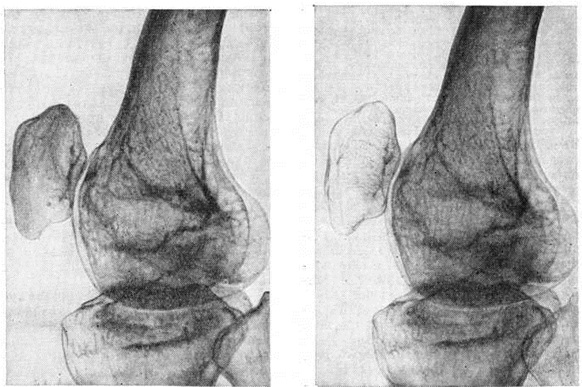

Рис

Рентгенограмма коленного сустава в боковой проекции при атрофии Зудека атрофия: слева сустав до появления атрофии Зудека атрофия; справа выраженный остеопороз надколенника

Прижизненное распознавание, определение характера и степени распространения Зудека атрофия возможно только с помощью рентгенографии. Учитывая разрежённость костной структуры, снимки производят «мягкие». Глубокие нейротрофические изменения тканей при Зудека атрофия на рентгенограмме проявляются в довольно быстром (спустя 7—10 дней от начала заболевания) возникновении остеопоротической перестройки костной структуры, имеющей вначале мелкоочаговый характер (рисунок). Густо сидящие, мелкие, округлой формы очажки разрежения придают костной ткани пятнистый вид. В дальнейшем в связи с быстрым нарастанием процессов рассасывания преимущественно второстепенных и поперечных костных балок и истончения кортикального слоя остеопороз приобретает диффузный характер, на фоне которого отчётливо видны системы костных балок, расположенных по силовым линиям и несущих основную функциональную нагрузку.